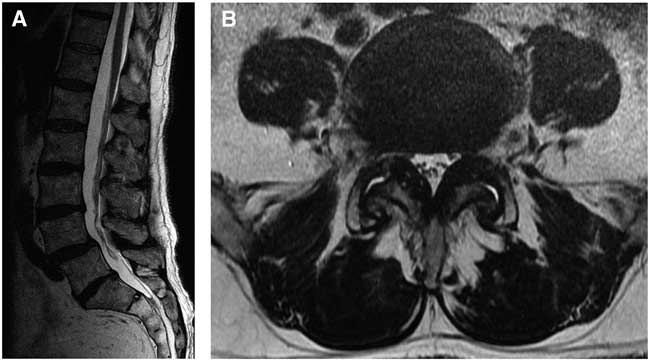

A 72-year-old male presented after 10 years of increasing bilateral claudicant leg and lower back pain. Conservative management including physiotherapy, chiropractic manipulations, and uncomplicated epidural steroid injections had failed. Medical history was positive for non-insulin-dependent diabetes mellitus, and he was not on any anticoagulation therapy or acetylsalicylic acid. Preoperatively, his leg pain was 8 of 10 in severity and he scored 25 of 100 on the EuroQol 5D Health Scale. Physical examination revealed grade 4 of 5 weakness in the L5 myotome bilaterally. Preoperative needle electromyography revealed decreased activation of the peroneal muscles and borderline slowing of motor conduction velocity. No signs of myelopathy were present. Preoperative radiological investigations performed before and following epidural injections showed degenerative grade 1 spondylolisthesis at L4-L5 (Figure 1A, B) and no signs of intradural pathology. Dynamic flexion-extension radiography demonstrated instability at this level.

Figure 1 Preoperative T2 weighted sagittal (A) and axial (B) MRI scans from T10 to sacrum showing L4-L5 degenerative spondylolisthesis and lateral recess stenosis. No intradural pathology was noted.